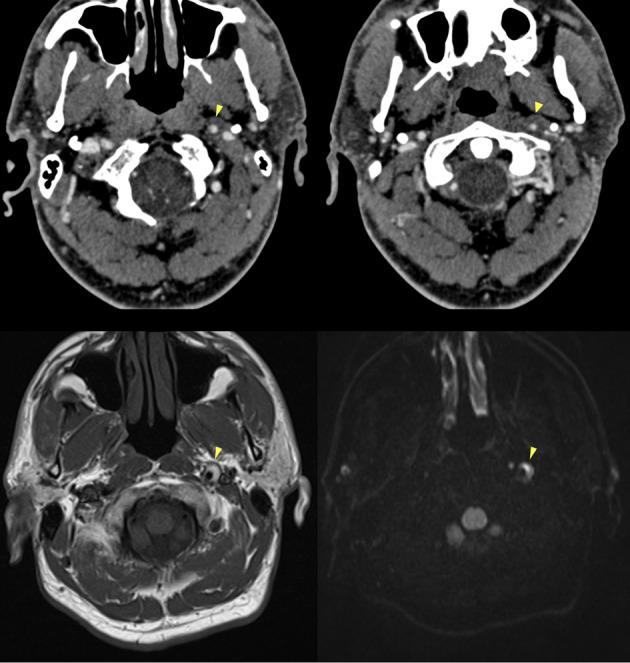

The objective of this work is to describe the possible cerebrovascular complications of critically ill traumatic brain injured patients and to understand the most common underlying mechanisms and radiological features as well as their management. A variety of pathological entities will be addressed, such as post-traumatic aneurysms, carotid-cavernous fistula, arterial occlusion, arterial dissection (in potential association with brain ischemia), as well as arterial rupture/avulsion and post-traumatic venous thrombosis. Neurovascular complications of head trauma vary depending on the traumatic mechanism, on the site of impact and on the osseous structures involved. Early diagnosis is mostly based on Computed Tomography/Computed Tomography Angiography (CT/CTA) whose findings help guide patient management by detecting vascular lesions potentially leading to neurological deterioration. Magnetic resonance imaging may be useful in selected cases. Today Digital Subtraction Angiography (DSA) is mostly a diagnostic problem-solving tool when CTA findings are equivocal but advanced endovascular interventional techniques have improved the therapeutic possibilities in post-traumatic vascular complications.  CONCLUSIONS: Neurovascular complications are not common after head trauma but should not be overlooked because they might lead to severe and life-threatening consequences. Early diagnosis, and a multidisciplinary collaboration including neuroradiologists, neurosurgeons and neurointensivists is fundamental in order to prevent and minimize secondary brain damage in this population.

这项工作的目的是描述重症创伤性脑损伤患者可能出现的脑血管并发症,并了解最常见的潜在机制、放射学特征及其治疗方法。将探讨多种病理实体,如创伤后动脉瘤、颈动脉海绵窦瘘、动脉闭塞、动脉夹层(可能与脑缺血相关),以及动脉破裂/撕裂和创伤后静脉血栓形成。头部创伤的神经血管并发症因创伤机制、撞击部位和所涉及的骨性结构而异。早期诊断主要基于计算机断层扫描/计算机断层扫描血管造影(CT/CTA),其结果有助于通过检测可能导致神经功能恶化的血管病变来指导患者的治疗。在某些特定情况下,磁共振成像可能有用。如今,当CTA结果不明确时,数字减影血管造影(DSA)大多是一种解决诊断问题的工具,但先进的血管内介入技术已改善了创伤后血管并发症的治疗可能性。